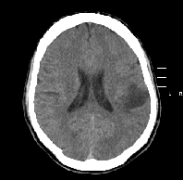

显微外科和神经成像技术、术中神经生理监测和神经导航,可能有助于好转原发性脑干出血患者的预后。然而,手术治疗的效果仍有争议...